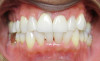

Fig 13. After completion of treatment, improved anterior esthetics and replacement of upper restorations were achieved.

Figure 13

Fig 14. After completion of treatment, improved anterior esthetics and replacement of upper restorations were achieved.

Figure 14

During a dental hygiene examination, aligner treatment was suggested to a patient, a 49-year-old man who presented with mild to moderate lower arch malocclusion with anterior crowding. At the time, concerns of a missing lower molar, combined with posterior and anterior malocclusion, were raised to the patient (Figure 5 through Figure 12). The patient's options included a restorative treatment with a lower missing molar, and replacement of the upper anterior arch crown restorations along with clear aligners. The patient did not wish to spend $4,000 to $5,000 on full orthodontics at that time. Once the need to remove the heavy anterior occlusion to gain better overjet for the longevity of the periodontal and restorative prognosis was explained, the patient decided to move forward with the clear aligners, limiting aligner treatment primarily on the anterior arch as an esthetic approach. To avoid losing the patient, this office decided to provide limited aligner treatment for less than $2,000 to address the anterior esthetics. Aligner treatment took longer than expected, requiring more aligners at an additional cost that was not charged to the patient. The delay in finally gaining lower cuspid rotations, along with resolving the lower anterior crowding to gain better esthetics before the delivery of the upper restorations, required over 20 aligners and took more than 15 months to complete. Patient motivation and compliance were also an issue, because the patient was required to report for numerous follow-up visits regarding aligner wear. Extended treatment meant that frequent office visits were necessary, adding additional chair time that had not been anticipated. After initial consultation, completion of the initial treatment plan (improved anterior esthetics with the replacement of upper restorations) took almost 2.5 years (Figure 13 through Figure 20).

In hindsight, the practice perhaps should have taken a different approach, given today's hybrid option, which helps better ensure that the patient remains motivated to continue with clear aligner treatment and tracking. Had the hybrid approach been applied in this patient, the practice would still have benefitted financially, as it would have been compensated for services, with chair time reserved for other restorative work, while gaining a new patient.